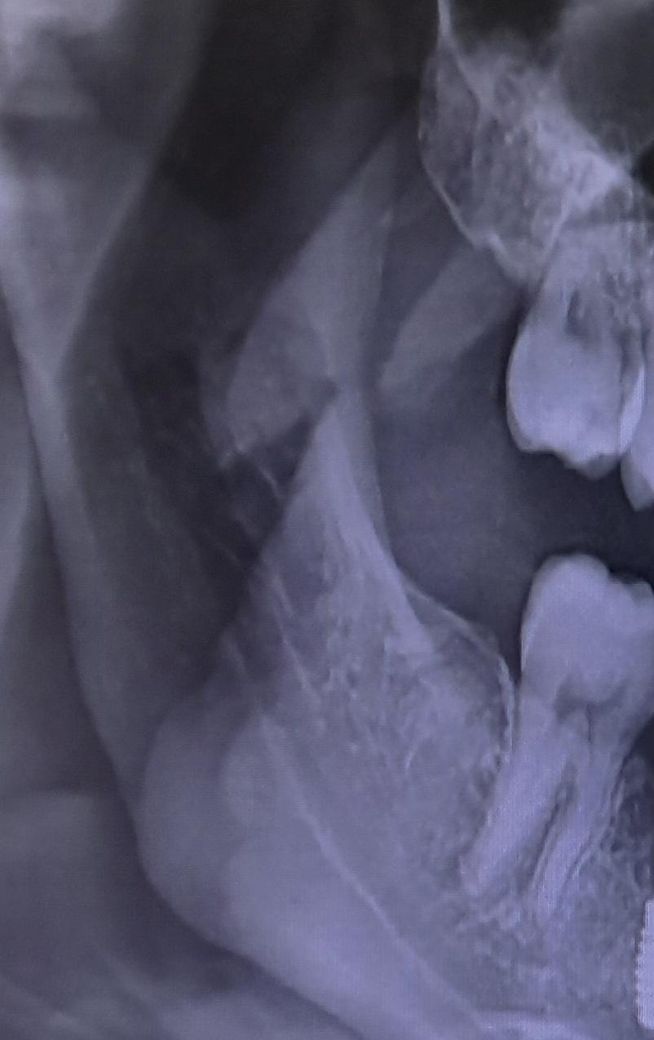

어금니를 지아이로 치료받았는데 사기당한 건가요??

위아래 어금니에 교접하는 부분에 충치가 있다고해서 치료받았습니다. 근데 추가적인 설명없이 gi로 해주셨는데 인레이나

레진으로 했어야하는게 맞는건가요???

• 1번 째 사진

gi경우 보험되는 재료입니다. 작성자분이 gi가 맘에 들지 않는다면 가셔서 레진으로 교체를 하시면될것같습니다 엑스레이 상으로는 충치가 깊은거 같지는 않습니다.